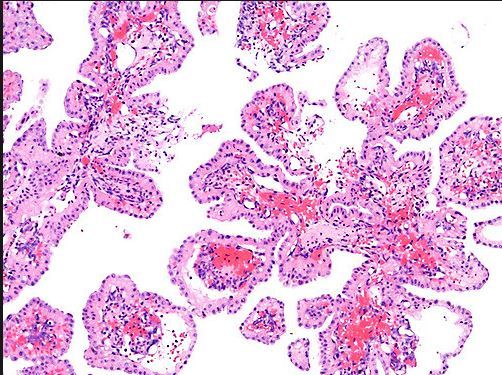

Which ear tumor arise in the temporal bone, is benign, locally destructive, rare, M=F, 2nd – 8th decade, has association with VHL disease, is papillary and cystic with colloid-like material (PAS+), has bland cuboidal to columnar cells, eosinophilic to clear cytoplasm and is postive with keratin but negative for thryoglobulin?

Interestingly, the nuclei are situated AWAY from the base

Papillary Endolymphatic Cell Tumor which is also known as a Heffner tumor

D/D: PTC, RCC, adenoca, mid. ear adenoma